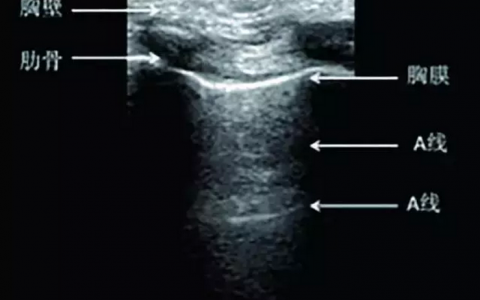

• 重症超声基础

肺脏由于含气量大,超声波不易穿透,易受胸骨和肋骨的阻挡,所以以往临床医生认为肺部是B超的禁区。但最近几年通过对超声影像的仔细辨认和借助超声伪像的征象,肺部B超逐渐在危重症患者床旁检查中流行起来。然而肺…